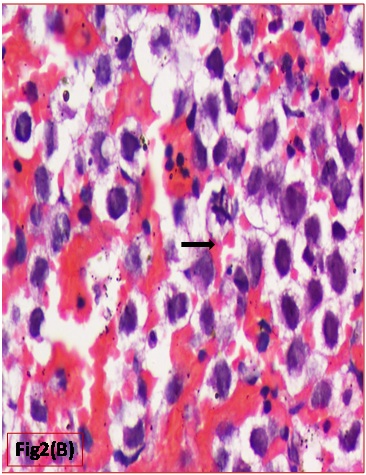

Histopathological evaluation showed a tumour with monomorphic large germ cells with enlarged centrally located vesicular nucleus, prominent nucleolus and moderate clear cytoplasm arranged in sheets, divided into lobules by fibrous septa with lymphocytic infiltrates and stromal hemorrhage; foam cells were also noted [Table/Fig-2a,b]. Also seen were immature glands lined by columnar cells with hyperchromatic nuclei and subnuclear- vacuolation surrounded by atypical spindle shaped stromal cells and foci of immature cartilage [Table/Fig-3]. Large areas of sinusoidal vascular channels surrounded by cytotrophoblasts and syncytiotrophoblasts were seen suggestive of choriocarcinoma [Table/Fig-4a,b].

Immature gland lined by columnar cells with hyperchromatic nuclei representing Immature Teratoma (H&E: 200X)